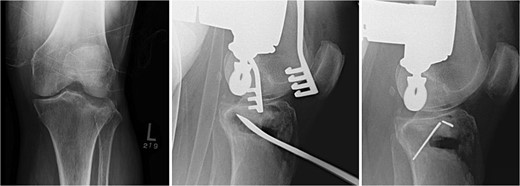

The void left in the lateral tibial condyle after elevation of the articular surface is usually triangular in shape. The depth and lateral height are measured. A tricortical iliac crest allograft is selected and cut to an appropriate size based on these measurements. The allograft is then inserted parallel to the joint surface to raft the articular surface. They usually fit nicely thanks to the natural triangular shape of the allograft (Fig. 2).

Tricortical iliac crest allograft preparation, measurement, cut to an appropriate size, and insertion into the defect.